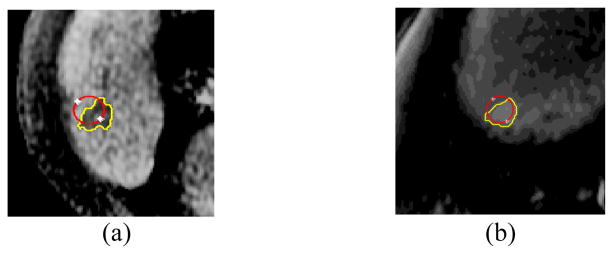

Fig 2.

Adaptive local window sizes estimated for different lesions and different contour points. For each image, the adaptive local window size chosen is shown for two different contour points (a) Low contrast MRI liver lesion. Yellow window – 2.4 mm × 4 mm, green window – 4 mm × 4 mm. (b) Noisy CT liver lesion. Yellow window – 8 mm × 8 mm, green window – 7 mm × 9 mm. Red contour – radiologist manual marking. White contour – initial zero level set (ZLS) contour.